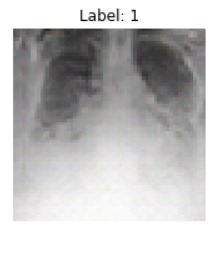

With an x-ray image of an individual's healthy lungs, we are able to use machine learning techniques to add features indicative of COVID-19. Given that we're handling an image, we took an approach that applied the use of Generative Adversarial Networks (GANs) to create a new image of the same lungs except with added COVID-19 properties. COVID-19 may manifest in an x-ray as cloudy regions in the lungs, known as ground glass opacities.

We built an Auxiliary-Classifier GAN (arXiv:1610.09585) that produces lung x-rays with or without COVID-19 properties based on an inputted condition. After the generator has been trained, an inputted healthy lung x-ray is encoded into a latent vector via gradient descent with a VGG perceptual loss (arXiv:1802.05701, arXiv:1603.08155). Then, a condition vector is concatenated with this latent vector and run through the generator to produce the same lung x-ray but with COVID-19 ground glass opacities. This model was written in Pytorch. Hyperparameters and code can be found at the following GitHub. The training data included around 2000 total 64x64 COVID positive and negative x-rays.